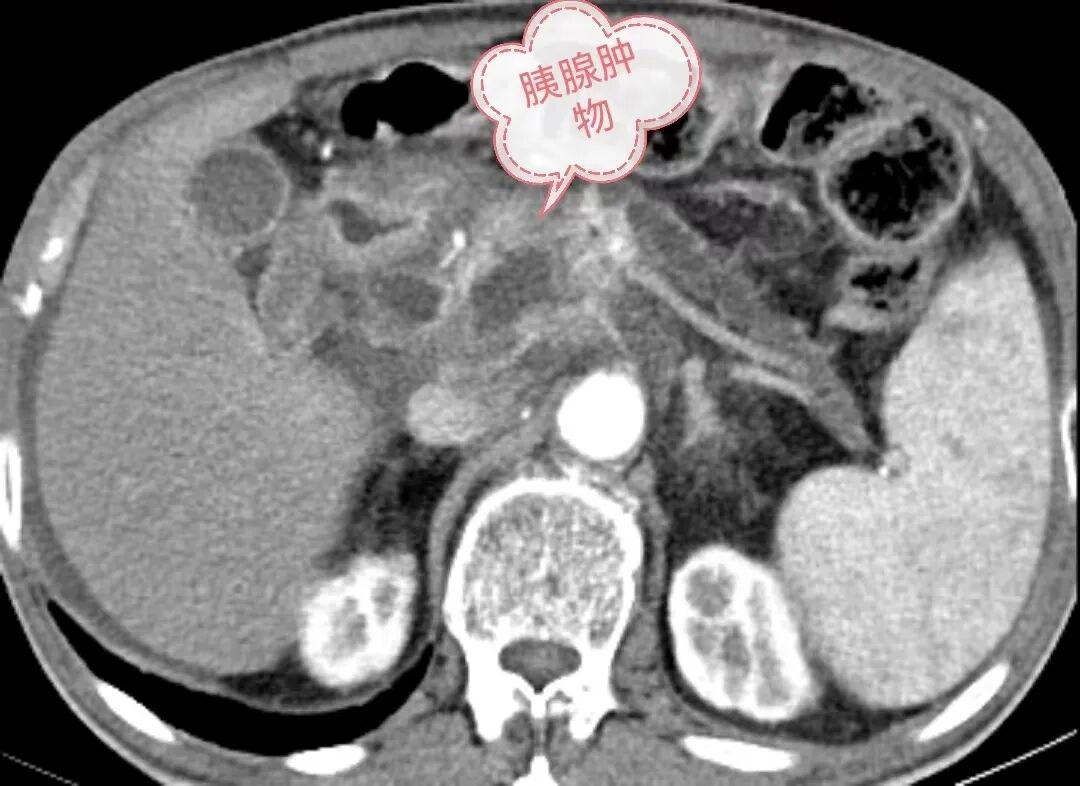

近日,赤峰市医院CT室微创介入团队成功为一名胰体占位患者实施了CT引导下胰腺穿刺活检术,经病理检查确诊为胰腺癌。在肿瘤诊治方面取得的一大突破。

患者,男性81岁,上腹痛半年,当地医院检查发现胰腺占位性病变,遂转入赤峰市医院进行治疗。入院后经CT和磁共振成像检查,但胰腺病变仍未明确,须行穿刺活检术进一步确诊。“穿刺活检术一般有CT、 超声、MRI、X光透视引导,而胰腺周围有胃肠道遮挡,超声引导受肠气及距离的影响,有一定局限性。”赤峰市医院CT室主任丁国成介绍,MRI引导价格昂贵,DSA引导因其密度、空间分辨力低,对胰腺穿刺更是禁忌,CT机以其高度的密度分辨力,强大的后处理功能,成为穿刺活检术重要的引导手段。

胰腺肿块穿刺活检是胰腺肿瘤诊断的金标准,然而胰腺解剖位置复杂,穿刺中要避开神经、血管和周围脏器组织,穿刺风险大,极易因操作不当、术前准备不充分等原因出现肠穿孔、胰瘘、腹膜炎等严重并发症,故该项检查是一项高、精、尖的检查技术。为明确诊断,微创介入团队反复研究穿刺方案及其可行性,最终认为本病例有一定的操作空间。在征求患者同意后,决定为其实施胰腺穿刺活检术。

“胰腺位于人体腹部的中心,前有胃肠道覆盖,后有脊柱和肾脏阻挡,左有脾脏环绕,右有肝脏拦截,所以胰腺病变的穿刺活检极易损伤以上器官。另外,胰腺为人体中较大的腺体,血供极其丰富,胰腺头部有胰十二指肠动脉前、后弓环绕,胰腺体部和尾部有胰背动脉、胰大动脉呈梳状分支供血,这些血管纵横交错、相互交通成网,即使穿刺针到达胰腺附近,也很难避开这些血管。”丁国成解释说,该病例虽然肿块不大,但已侵及门静脉,引起静脉淤血,侧支循环形成,大量平时不开放的血管迂曲扩张,给本来就有难度的手术陡然增加了一定的困难。局麻后,在CT精确引导下,微创介入团队将套管针经皮穿刺,经多次方向调整,成功到达胰体肿块边缘,穿入活检针后精准取样,为患者顺利完成了这台高难度的穿刺活检术。